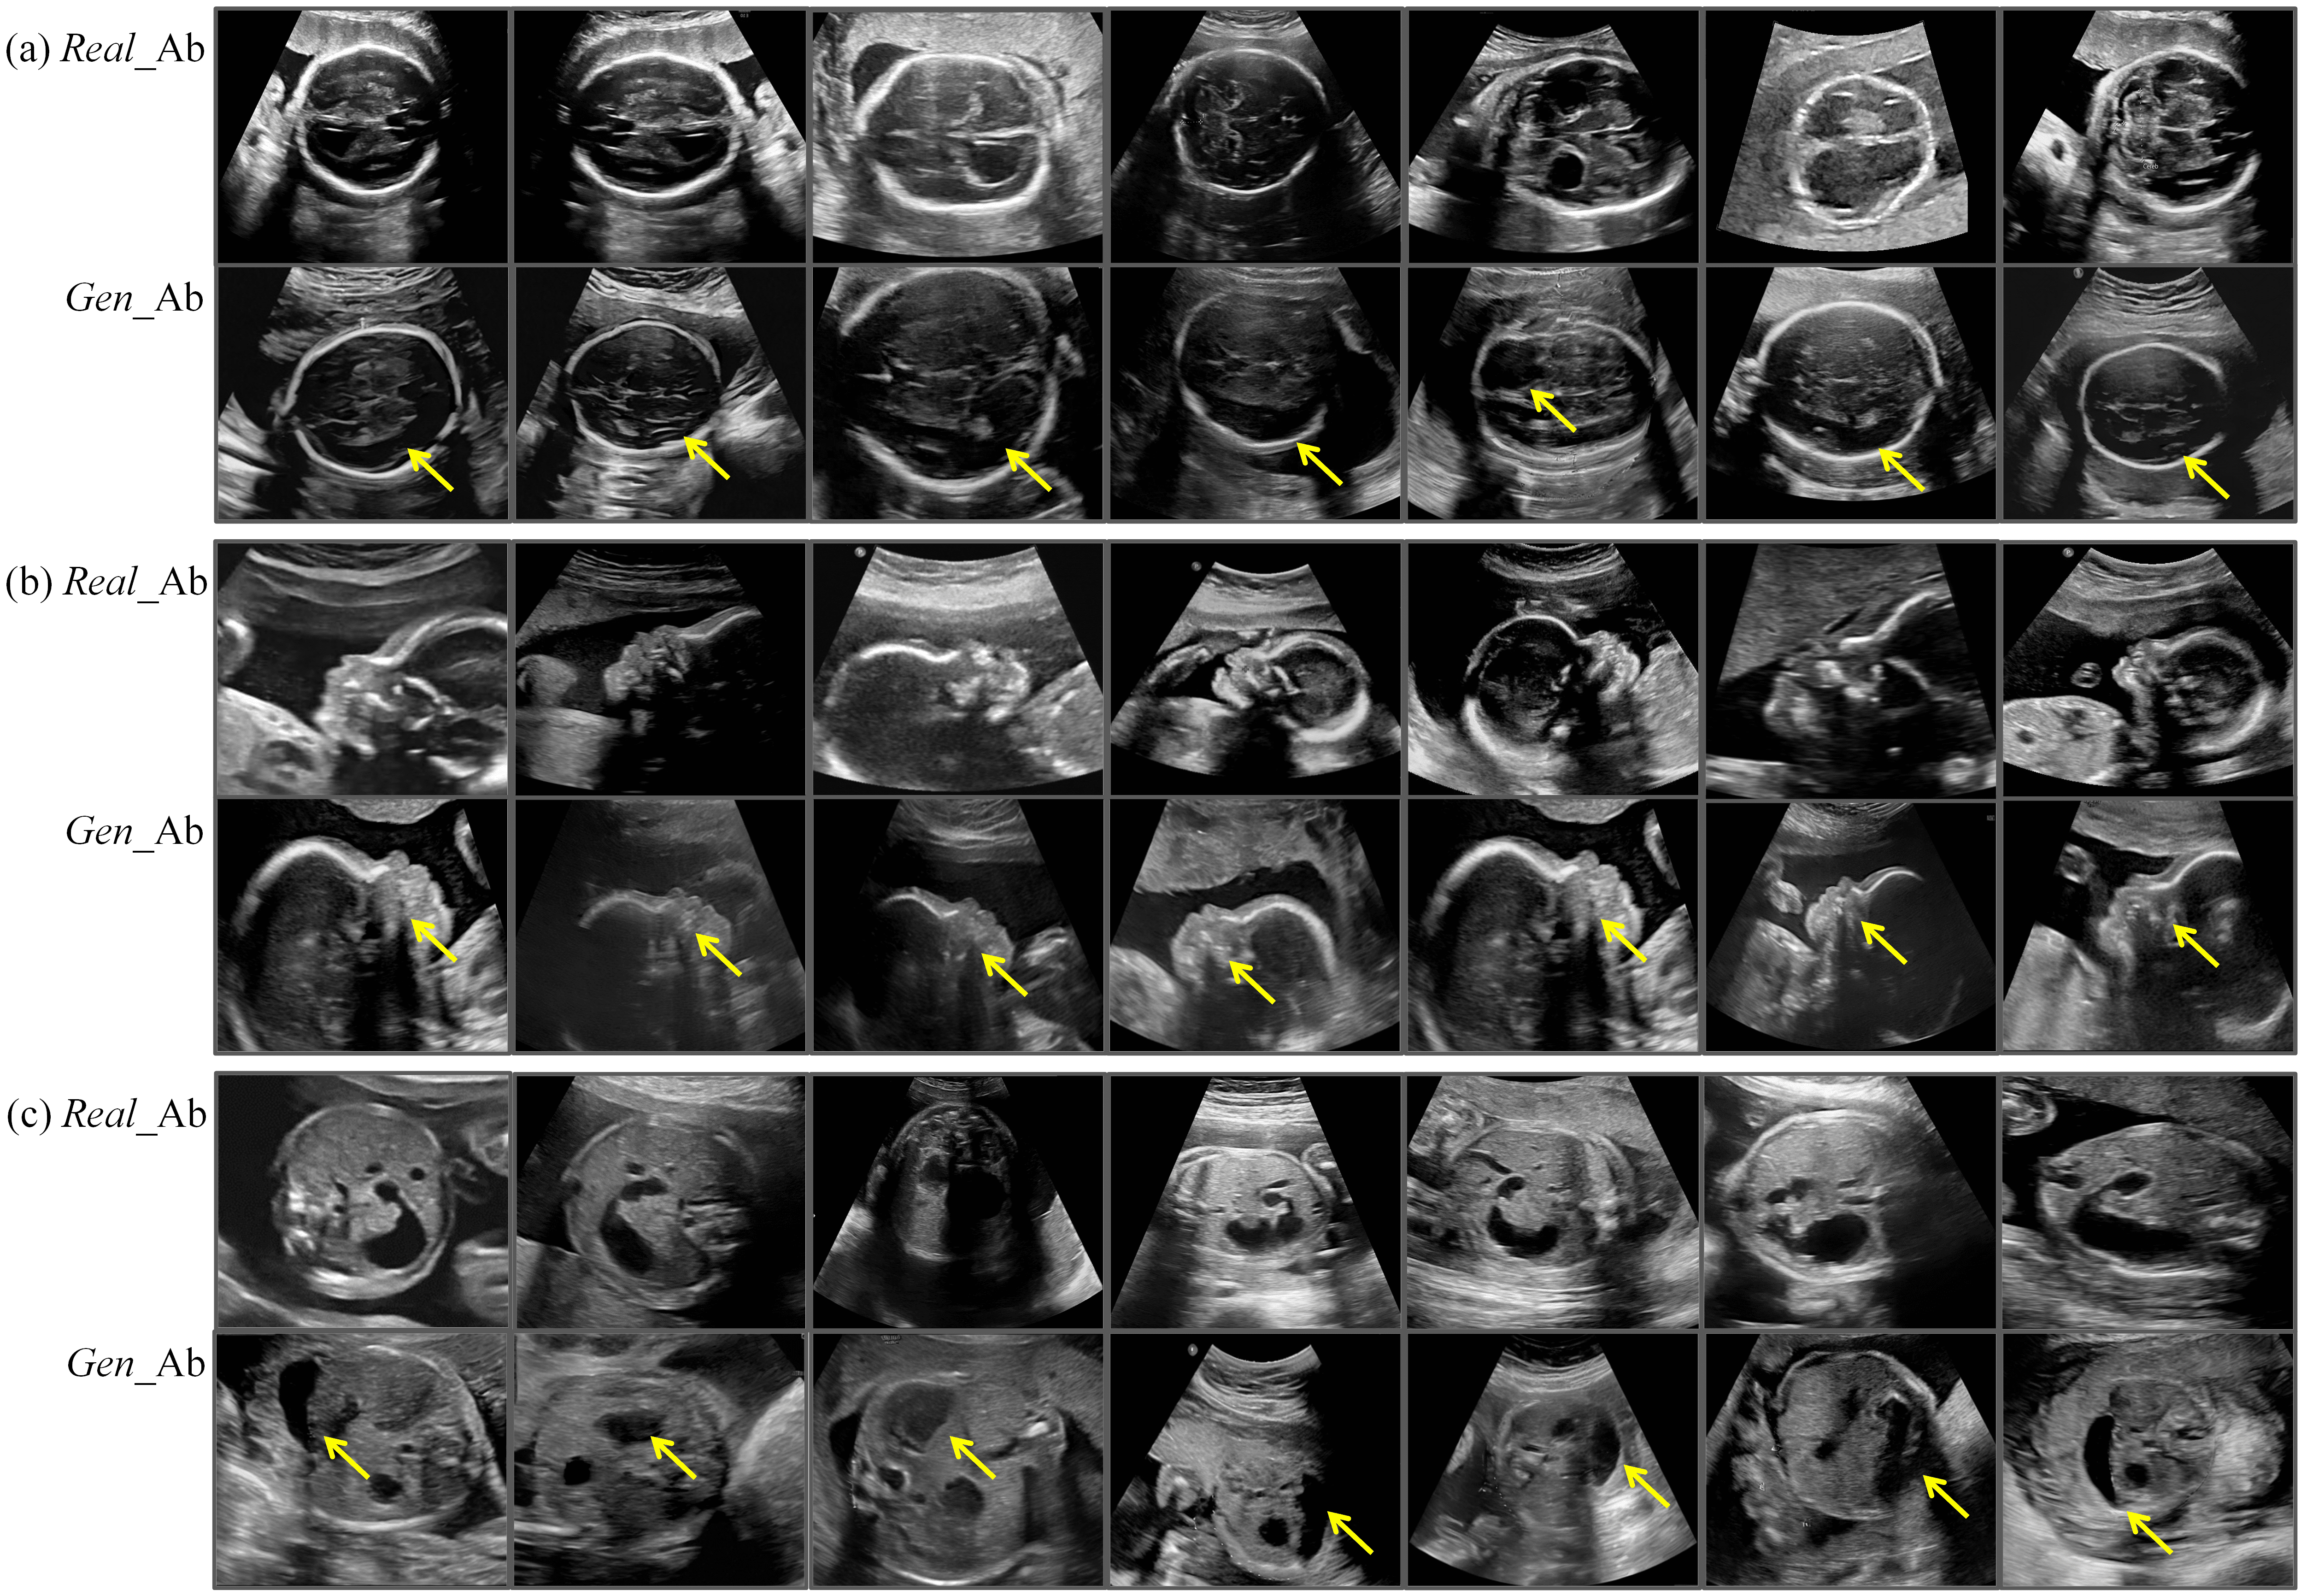

Figure 8: Real and generated abnormal fetal US images. (a) (b) (c) represent three different fetal US datasets. The first row displays a subset of real cases of hydrocephalus, the third row shows a subset of real cases of cleft lip and palate, and the fifth row presents a subset of real cases of duodenal atresia or stenosis. The second, fourth, and sixth rows correspond to abnormal samples generated by FetalFlex, where the yellow arrows indicate the anatomical structures that generate results similar to the real anomaly samples. Real_Ab: Real abnormal US images; Gen_Ab: Generated abnormal US images.

Moreover, we retrospectively collected 360 real abnormal samples of significant fetal malformations to construct the anomaly detection experiments for downstream tasks, with 120 abnormalities for each type of US plane. In detail, we collected real cases of fetal hydrocephalus in the thalamic dataset, samples of cleft lip and palate in the facial sagittal planes, and samples of duodenal atresia or stenosis in the upper abdominal transverse planes. Fig. 4 depicts typical normal samples in the dataset and abnormal US images with the aforementioned congenital malformations. These abnormal samples were diagnosed by experienced senior fetal US specialists according to the ISUOG and PPUS guidelines mentioned above.

It is important to note that in actual clinical prenatal screening, the types of fetal anomalies are highly diverse, involving multiple anatomical structures and physiological systems. This complexity causes challenges in retrospective data collection owing to the difficulty in covering all possible types of anomalies. Therefore, the retrospectively collected multi-center real abnormal dataset has certain limitations regarding the representation of anomalies across different fetal planes. In detail, the dataset for the transverse thalamic plane contains only cases of hydrocephalus, the facial sagittal plane dataset includes only fetuses with cleft lip and palate, and the upper abdominal transverse plane dataset is limited to cases of duodenal atresia or stenosis. For this reason, we instructed FetalFlex to perform a high-quality synthesis of abnormalities for the anatomical and structural manifestation characteristics of the abovementioned diseases. We visualized the real clinical anomaly data collected alongside the abnormal samples generated by FetalFlex, as shown in Fig. 8. By adjusting the control conditions, FetalFlex was able to generate US images that closely resemble the abnormal in real cases, allowing our proposed method to achieve cross-domain generation at the image-level.